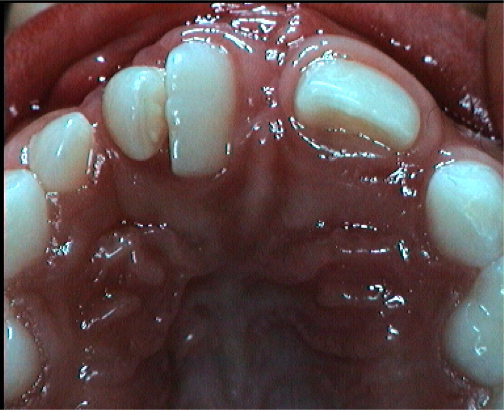

Fig 2. The lateral incisor is absent or malformed in most cases (76%) or has abnormalities of size and / or shape (> 95%). The problem number one is: should we replace this tooth with an implant or rather try to close the space by moving the neighbouring teeth in its place by orthodontic means? One of the most extensively debated topics.

Fig 2. The lateral incisor is absent or malformed in most cases (76%) or has abnormalities of size and / or shape (> 95%). The problem number one is: should we replace this tooth with an implant or rather try to close the space by moving the neighbouring teeth in its place by orthodontic means? One of the most extensively debated topics.